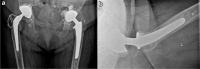

With the increased use of dual-mobility cups (DMCs) in total-and revision hip arthroplasties, surgeons can expect an increase of known and new complications. During routine follow-up, we observed an asymptomatic patient with an intraprosthetic-dislocation (IPD) and elevated levels of serum metal ions (1.8 ppb of cobalt and 28.0 ppb of chromium). Revision surgery was inevitable. Perioperative metallosis and severe wear of the metal shell and metal femoral head supported the IPD. Literature showed that the modularity of the DMC can result in increased serum metal ions, create excessive wear, and possibly affect implant survival. Our case and review of the literature may form an argument not to consider DMC for primary cases. Furthermore, we advise yearly clinical and radiological follow-up and, on indication, metal ion testing for DMCs.